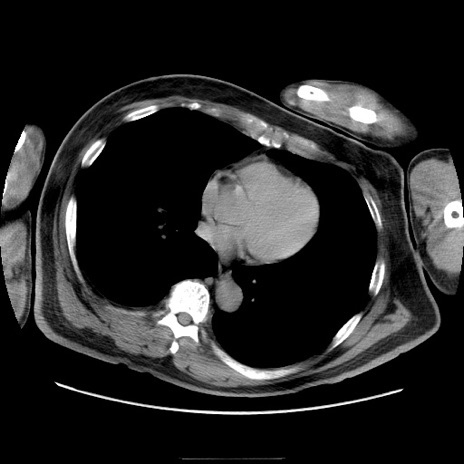

症例22(横断像)

【症例】50歳代男性

【主訴】腹痛

【現病歴】AVMからの被殻出血のため回復期リハ病棟入院中。 本日午後3時頃急に下腹部痛が出現した。

【既往歴】AVM、被殻出血、虫垂炎、高血圧

【身体所見】意識晴明、左半身不全麻痺、会話の理解は良好、36.5°C、腹部:膨隆、全体に板状硬、下腹部正中に圧痛点あり、反跳痛-、筋性防御不明、右下腹部にope scar

【データ】WBC 9400、CRP 0.06